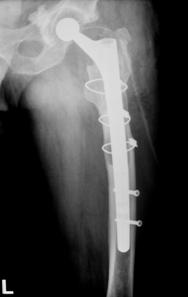

Proteza DLS.

Este o proteza din aliaj de titan, aluminiu si vanadiu (Ti6Al4V acoperita cu hidroxiapatita pe cea mai mare parte a lungimii sale, pentru a ajuta la fixarea ulterioara a protezei prin formarea de os la acest nivel.

Proteza prezinta o zona proximala rotunjita pentru o mai buna concordanta cu marele trohanter, un guler localizat medial pentru a marca nivelul penetrarii protezei in canalul femural, doua orificii localizate proximal in partea laterala a protezei pentru ancorare, un model asemanator solzilor de peste localizat anterior, posterior si medial pentru a ajuta osteointegrarea, un manson de hidroxiapatita ce se intinde pe doua treimi superioare ale protezei, treimea distala este neteda si lucioasa si este prevazuta cu doua orificii prin care se vor introduce suruburile de zavorare.

Privind din lateral proteza se poate observa forma anatomica a acesteia, proteza avand o dubla curbura pentru a se integra cat mai bine in canalul femural.

Suruburile de zavorare ce pot fi utilizate pot fi: cu fixare in corticala laterala, cu fixare in corticala mediala, cu fixare in ambele corticale. Dimensiunile suruburilor sunt intre 25 si 45 mm inclusiv, in incrementi de 5 mm.

Fig. Nr. 1.6. - Dimensiunile disponibile pentru protezele tip DLS[23]

Trei din cele 38 de solduri investigate au prezentat ca indicatie operatorie fractura periprotetica, doua solduri fiind diagnosticate cu fractura Vancouver B3, iar unul cu fractura Vancouver B2. Fracturile Vancouver B3 au fost tratate in ambele cazuri prin extractia protezei si introducerea unei proteze tip DLS de 275 mm lungime impreuna cu solidarizarea ansamlului folosind cate o placa si 4 cabluri in fiecare caz. Fractura Vancouver B2 a fost tratata prin extractia protezei si inlocuirea acesteia cu o proteza tip Modular.